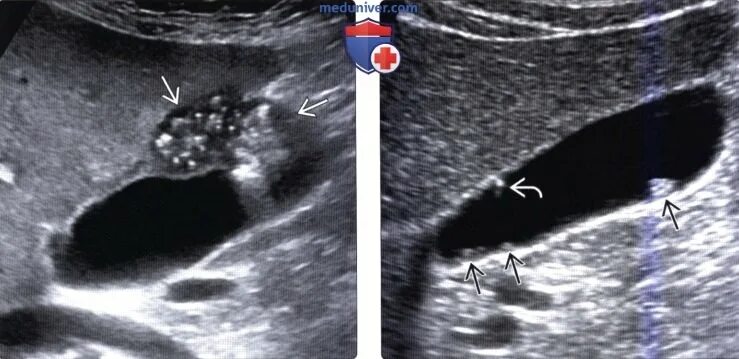

Изменение стенок желчного пузыря